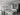

Sağlık Bakanlığı kalite yönetimine göre A Sınıfı (bölgenin en büyük kardiyoloji ve kalp damar cerrahisi) dal hastanesi olarak hizmet vermektedir. 40 standart oda, 2 engelli odası, 8 yatak üçüncü basamak Yoğun Bakım Ünitesi ,laminer floor sistemli 60’ar metrekare büyüklüğünde 3 ameliyathane salonu ve steril depo ,anjio salonu, röntgen, tomografi salonu bulunmaktadır.

Sağlık Bakanlığı kalite yönetimine göre A Sınıfı (bölgenin en büyük kardiyoloji ve kalp damar cerrahisi) dal hastanesinde tedavi olun.